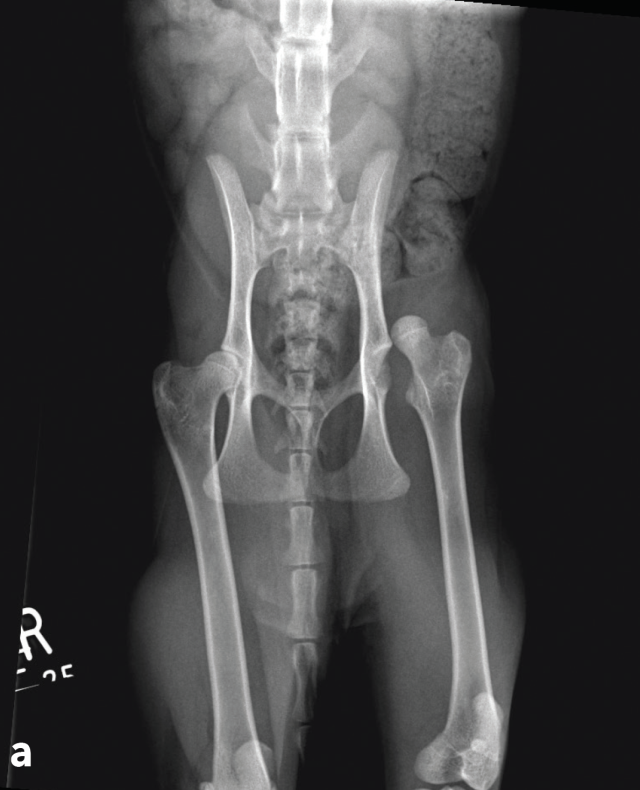

Comparison of complications and outcomes of cats with hip luxation treated with toggle rod technique using either ultrahigh-molecular-weight-polyethylene or nylon: a multi-institutional retrospective study

Coxofemoral luxation is frequently encountered in feline orthopaedic practice and is the commonest luxation in this species. A variety of surgical techniques have been described, with re-luxation rates ranging from 10-33%.1-4 Few studies have reported the use of toggle rod stabilisation for feline coxofemoral luxation.2,5,6 Very-good-to-excellent long-term outcomes were reported for 11 of 14 cats and a re-luxation rate of 14% in a study using polydioxanone.2 Excellent short-term outcomes were described for four cats using ultrahigh molecular weight polyethylene (UHMWPE).5 There are no large studies reporting use of UHMWPE or nylon for toggle rod stabilisation of hip luxation in cats, or studies that compare complications and outcomes of cats managed with UHMWPE or nylon.

The objectives of the study led by Dr Mullins are to describe the rate and type of intraoperative and postoperative complications and outcomes of toggle rod technique in cats, to compare the rate of complications and outcomes of cats treated with UHMWPE or nylon, and to identify risk factors for development of complications and non-excellent outcome. This will be a multi-institutional study involving ten referral centers. Outcome will be assessed based on the results of a designated telephone owner questionnaire.